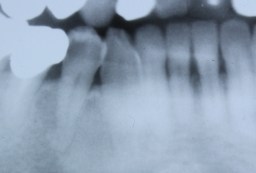

| 神経の部分の酸処理(エッチング)の影響を 避けるため、念のため、覆罩(ふくとう)して |

| レジンにて土台(レジンコア)を作り | ||

| 形成して仮歯(テック)を作ります。 |

上記のレントゲン写真。 神経もとらずに、治療が出来ます。 |